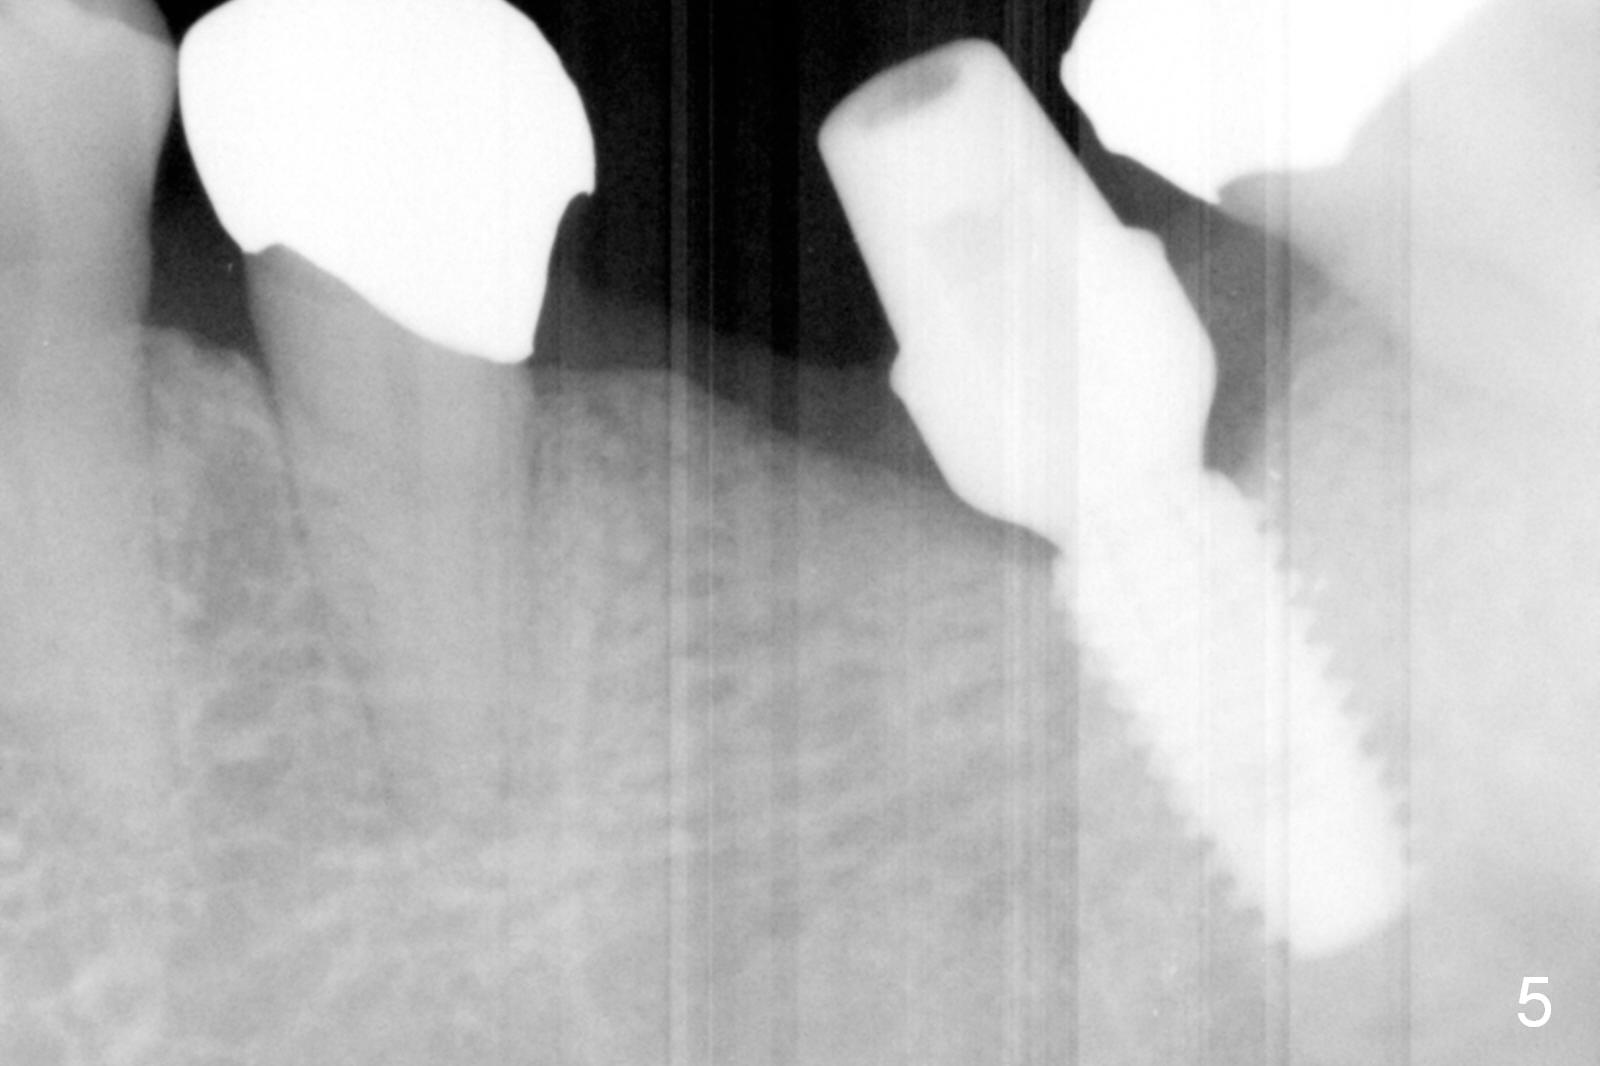

The narrow ridge top is trimmed until the buccolingual width is 7-8 mm; osteotomy starts in the flattened ridge (Fig.1, 2). A 5x10 mm implant is being placed (Fig.3). A cemented abutment (6.5x5.5(5) mm) is placed after adjusting the mesial and distal walls of the trimmed ridge (Fig.4). The patient returns for restoration 6 months postop. The coronal opening of the osteotomy becomes flared (Fig.5). The position and trajectory of the osteotomy should have been changed as early as possible (Fig.6, more or less parallel to the premolar) to avoid necessity of changing the cemented abutment (Fig.7 (* keratinized gingiva)) to an angled one (5.5 x15 degree A (4) mm).